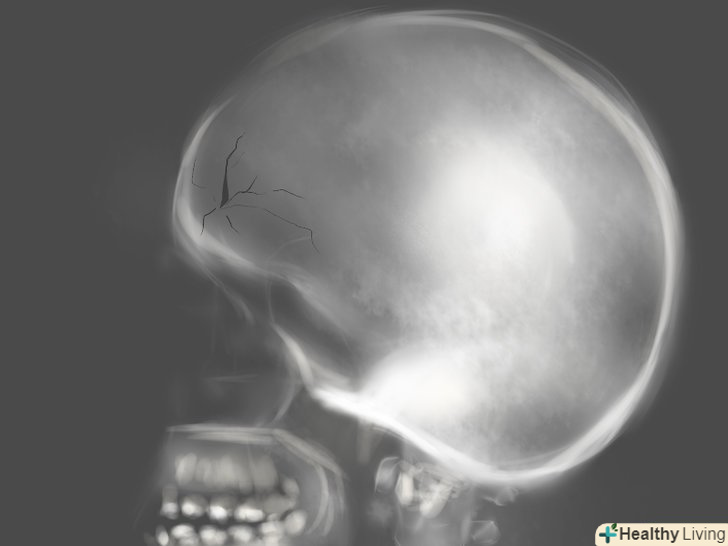

- Перевірте, чи немає переломів і тріщин кісток. якщо ви перенесли сильний забій обличчя, переконайтеся, що кістки під шкірою залишилися цілими. Це особливо важливо в разі порізу в результаті автомобільної аварії або дуже сильного удару. [11]